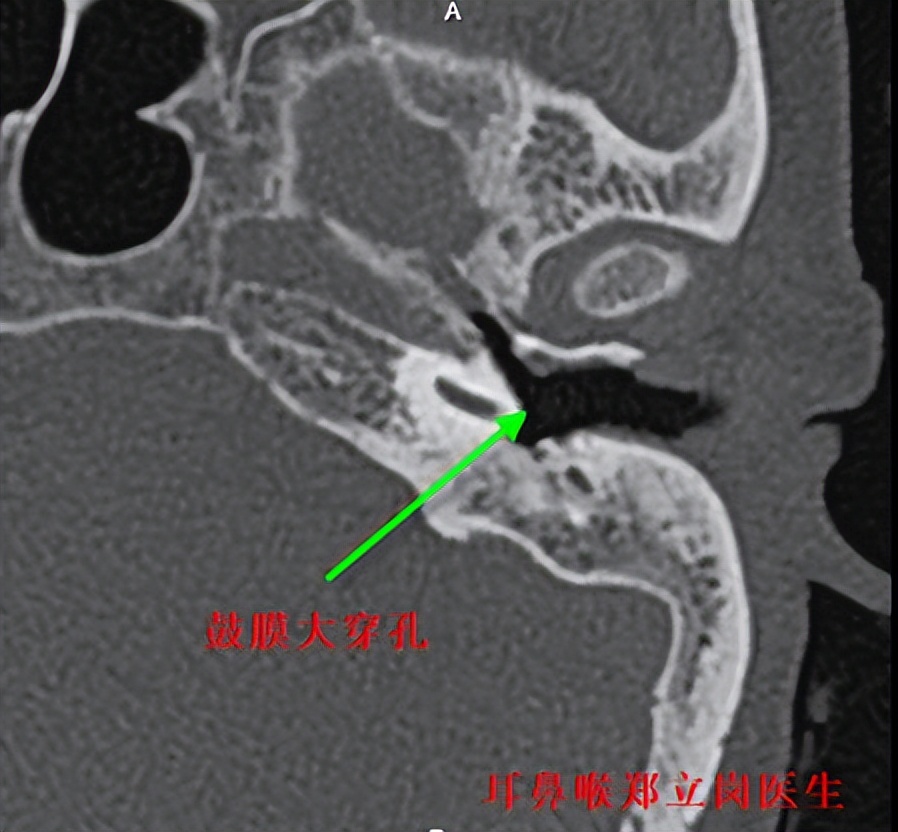

最近就有一位佛山禅城的患者找到耳鼻喉郑立岗医生,患者左侧鼓膜大穿孔,听力非常差。

这次做的是全麻耳内镜中耳炎微创手术,插管全麻后就开始了手术。在耳内镜下不用做任何的体表切口,直接翻起外耳道鼓膜皮瓣,翻起皮瓣后可以看到患者的砧镫关节是断裂的,镫骨底板上结构也是基本破坏没有了,镫骨底板完整,活动好。取出患者残余的砧骨和锤骨后,用钛质全听骨重建了听骨链,取合适大小的耳屏软骨修剪后修补了鼓膜。鼓膜修补好后检查了两遍确认没问题后就结束了手术。术后查房患者无明显的不适,无手术相关的并发症。